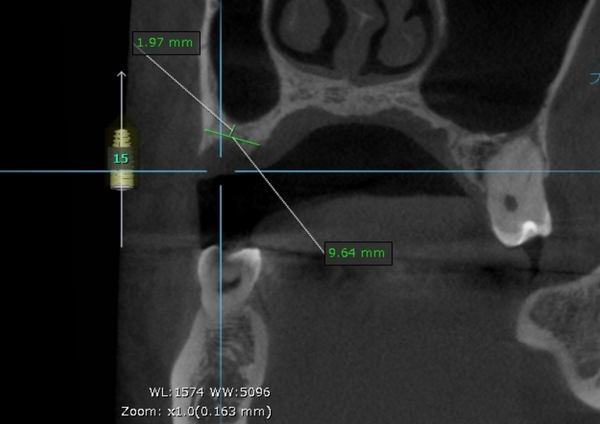

奥歯は歯根破折していたため、抜歯をし、骨が少なかったため上顎洞にサイナスリフトを行い、骨を補填してインプラントを埋入しました。インプラントブリッジにて被せ物を作りました。

治療期間 動的期間6ヶ月

費用 インプラント埋入2本 600,000円

サイナスリフト  330,000円

セラミックのブリッジ(クラウン3本分)  450,000円

合計   1,380,000円

治療によるリスク インプラントは歯周病に弱いため、歯周病にかかると悪化する可能性があります